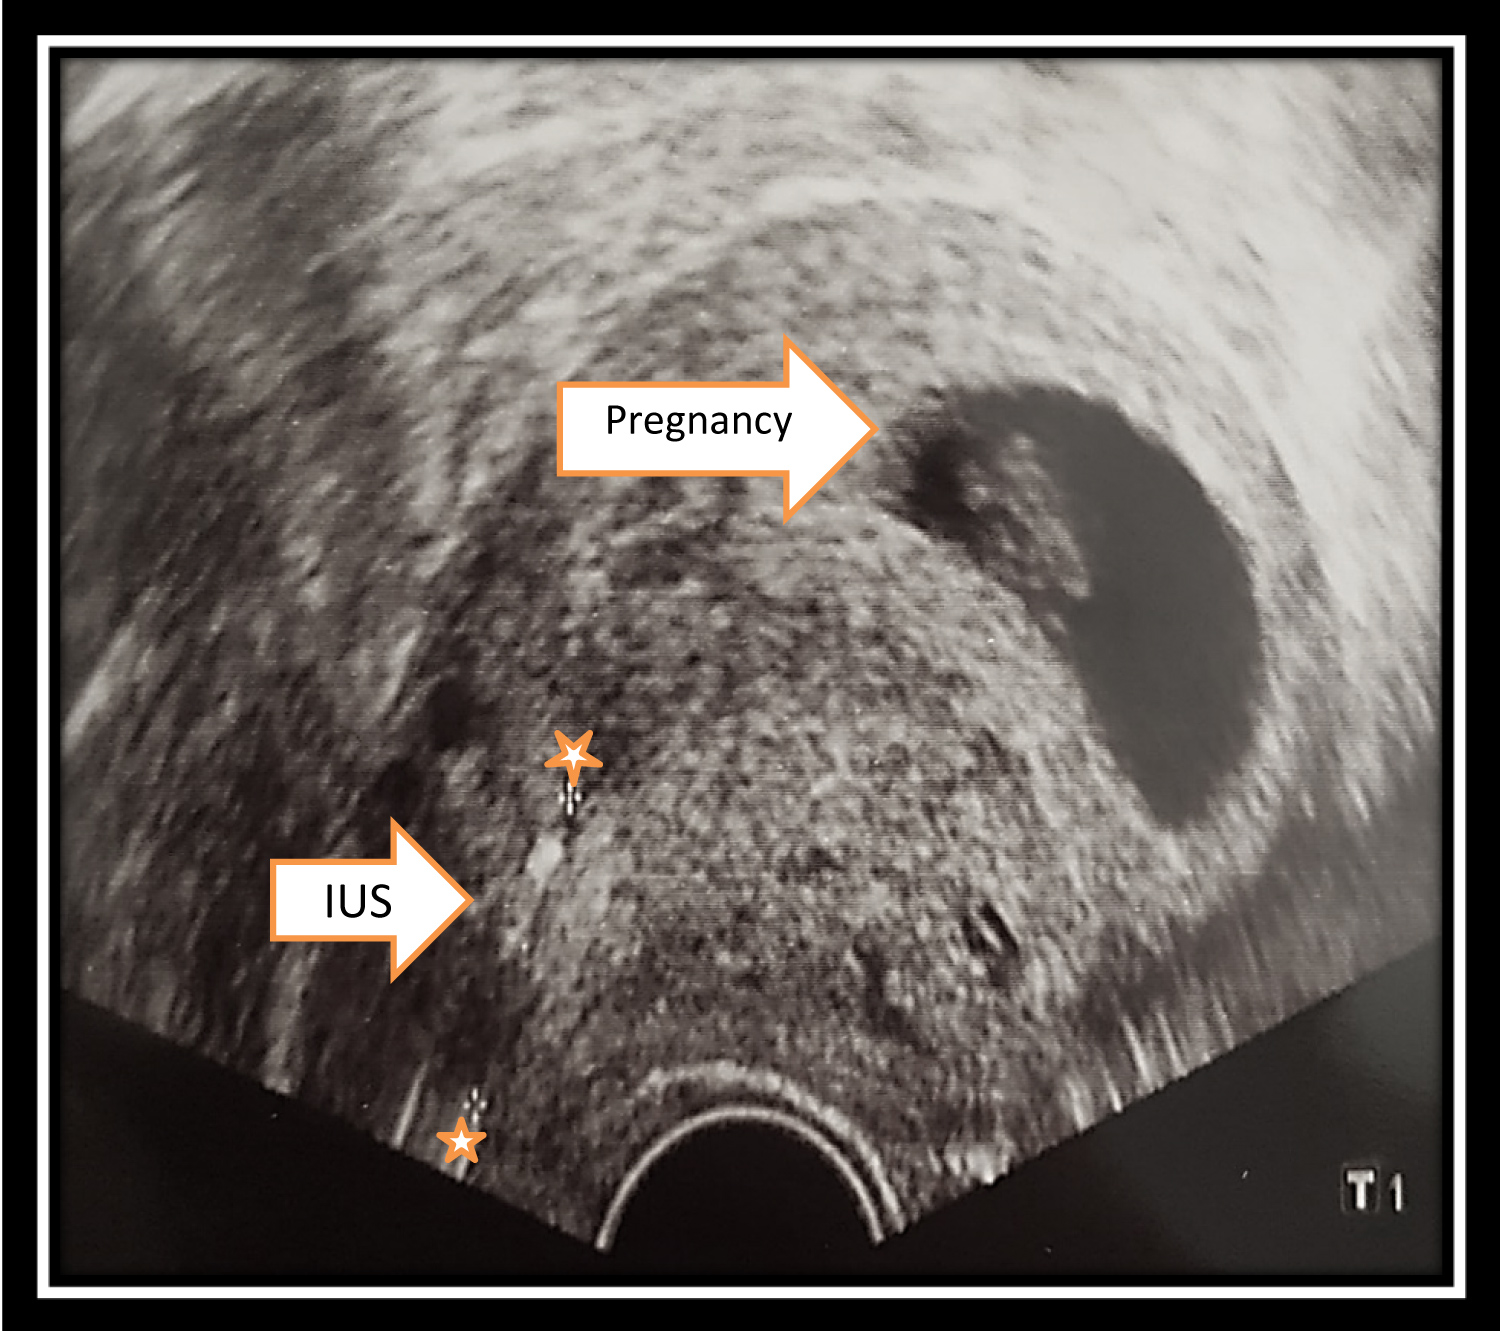

Case Report: Pregnancy While Using an IUD